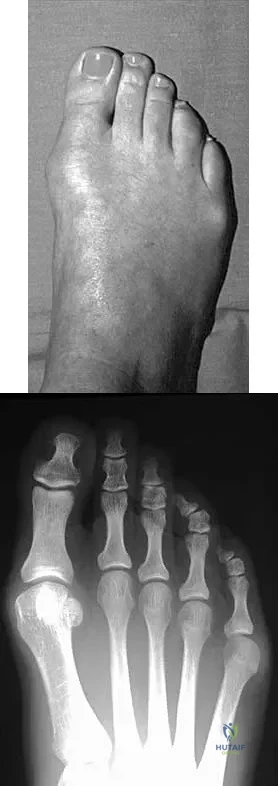

An active 47-year-old woman with rheumatoid arthritis reports forefoot pain and deformity and has difficulty with shoe wear. Examination reveals hallux valgus and claw toes. A radiograph is shown in Figure 10. What is the most appropriate surgical treatment?

Explanation

A 28-year-old woman has a moderate hallux valgus deformity and a prominence of the medial eminence. She can participate in all activities and reports that she could wear 3-inch heels in the past, but she now notes medial eminence pain even while wearing a soft leather flat shoe with a cushioned sole. She requests recommendations regarding surgical correction. Examination reveals a 1-2 intermetatarsal angle of 10 degrees. A clinical photograph and radiograph are shown in Figures 13a and 13b. What is the best course of action?

Detailed Explanation